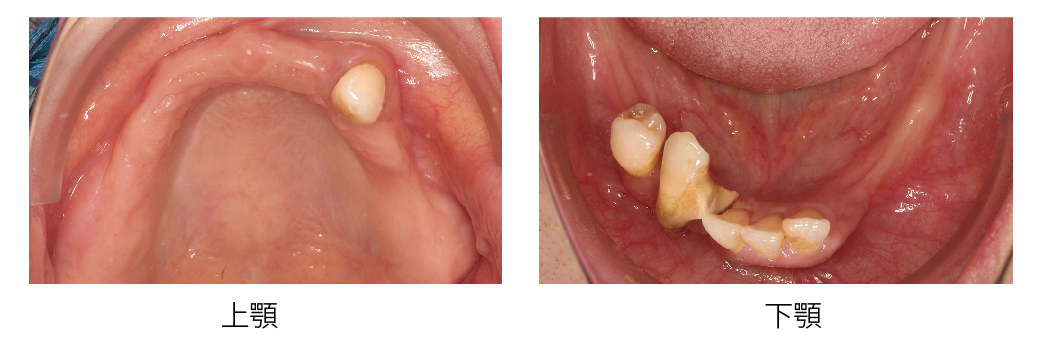

All-on-4/6 全口重建是一個很完整、系統性的治療流程,我們在開始之前,會先幫您做詳細的評估,包括拍攝X光、3D斷層掃描,還有口內外的檢查,來了解目前牙齒、骨頭和牙周的狀況,接下來,我們會根據您的需求和生活習慣,討論最適合您的治療方式。

▲從數位照片可以發現,上下顎缺牙狀況